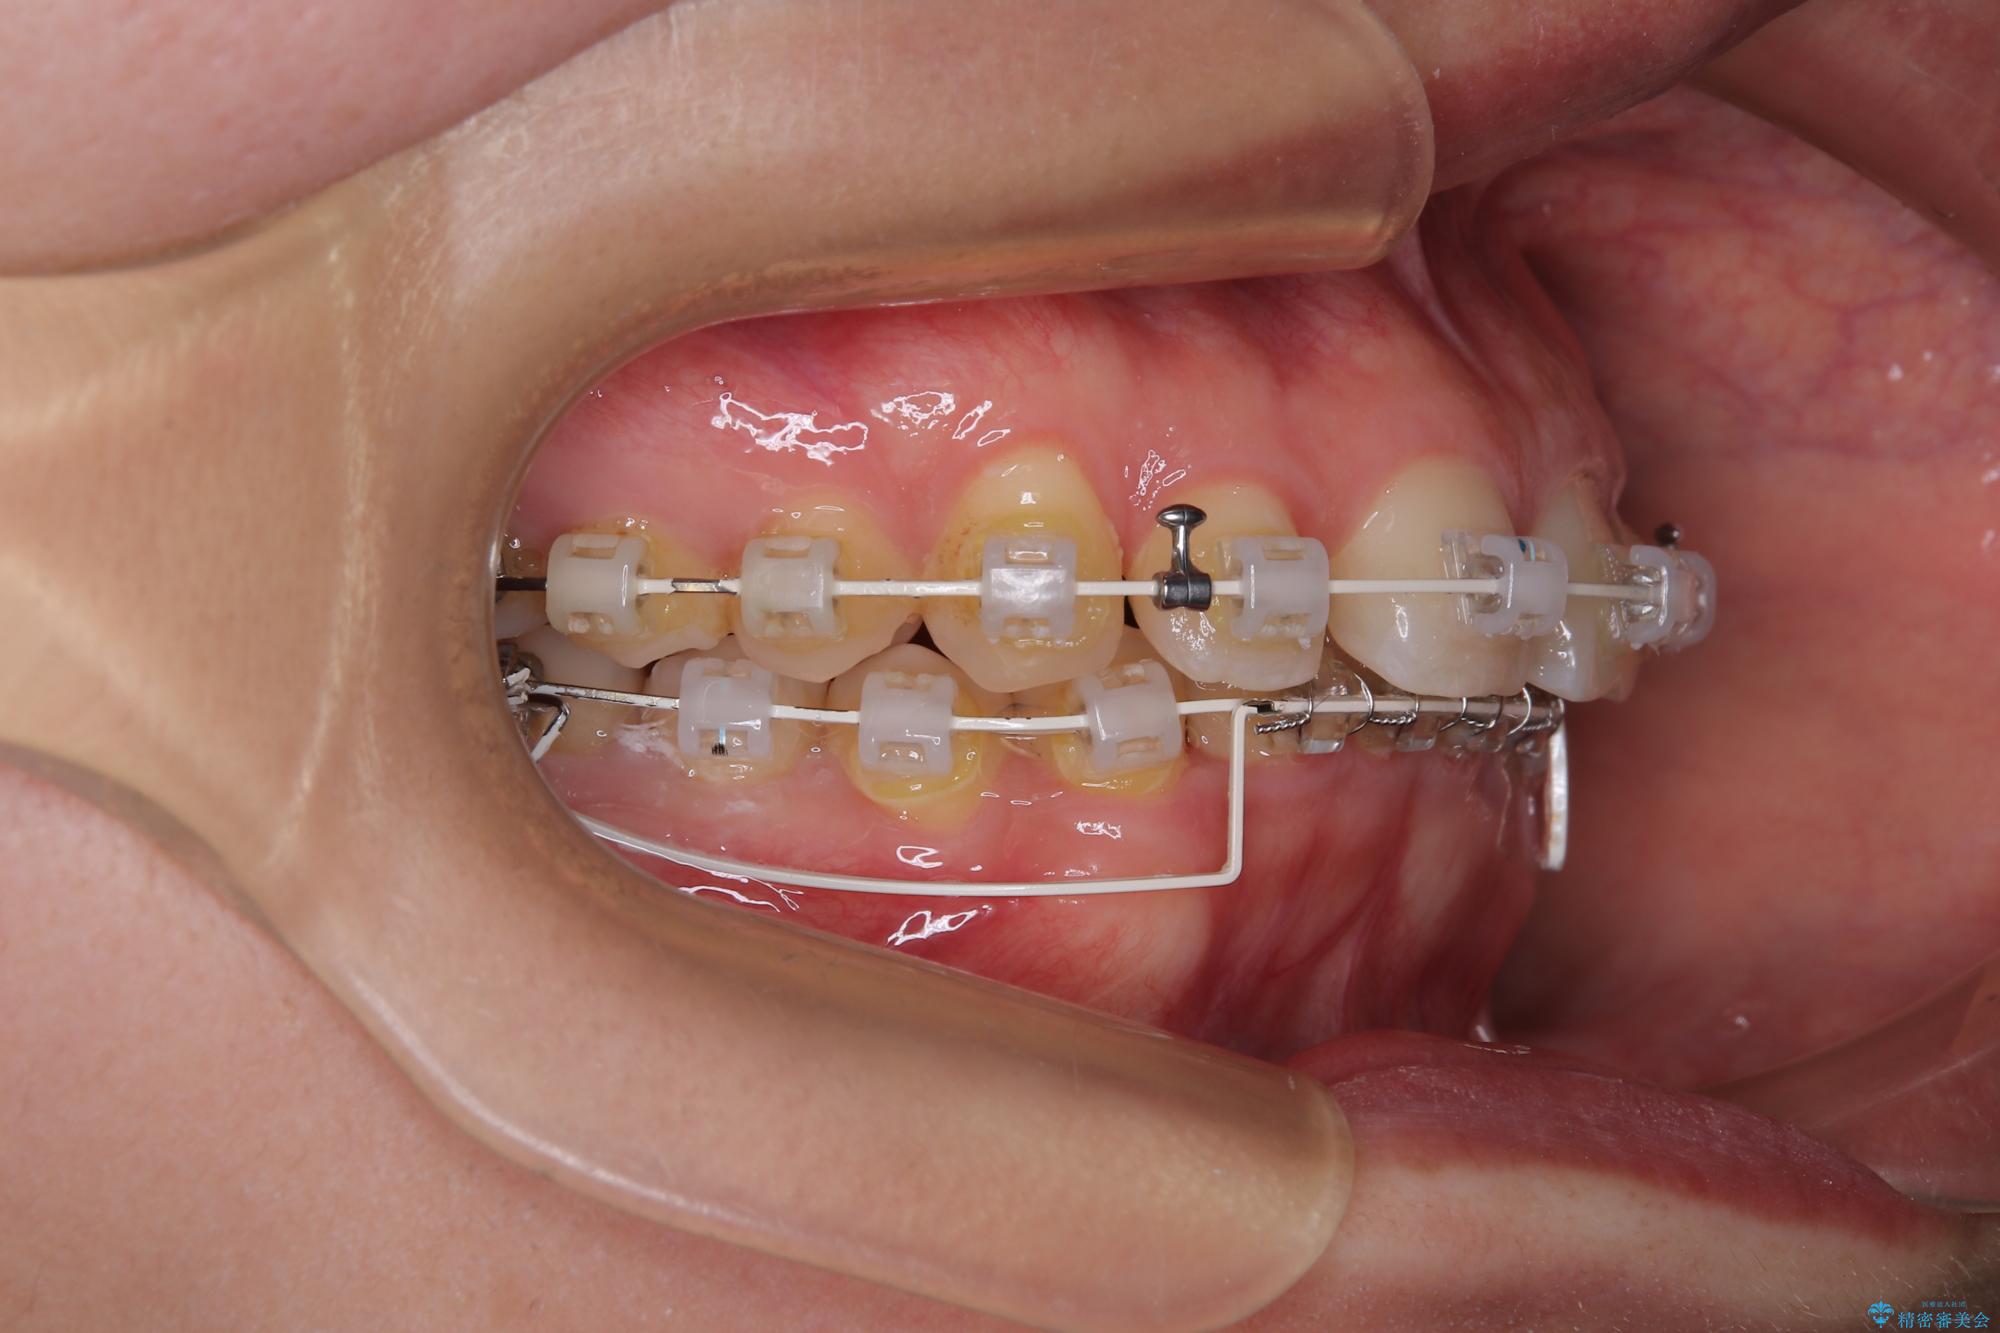

- 審美装置

下顎の臼歯が手前に傾斜していることで咬み合わせが深くなってしまい、下顎前歯が見えないほどに上顎前歯が覆い被さっている状態でした。

咬合力が強いことと、マウスピースを長時間装着する自信がないとのことで、ワイヤー装置にて矯正治療を行うこととしました。

下顎臼歯を起き上がらせるためにユーティリティーアーチを使用し、一気に深い咬み合わせを改善することができました。